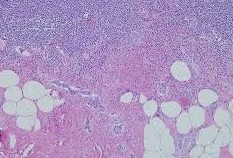

Μικροσκοπική εικόνα μετά από χρώση αιματοξυλίνης-ηωσίνης, που αναδεικνύει ινώδη συνδετικό ιστό χωρίς ατυπία, ομοιάζοντας με δερματικό ίνωμα (Ευγενική παραχώρηση Dr. V. Penopoulos)